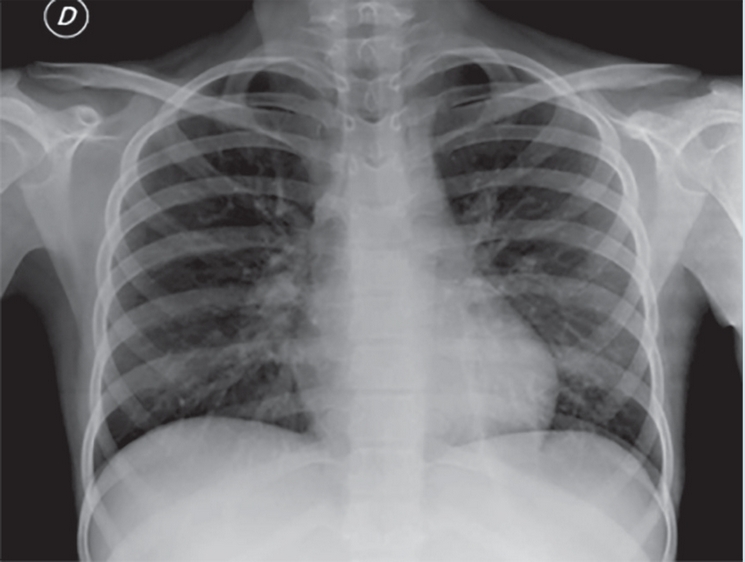

La valoración por Neumología documenta clínicamente disnea de moderados a pequeños esfuerzos, cianosis ungueal, taquipnea y oximetría de pulso de 76%, platipnea y ortodesoxia. La radiografía de tórax demuestra infiltrado intersticial reticular bilateral (Figura 1). Ante la presencia de hepatopatía crónica secundaria a lupus eritematoso sistémico y síndrome hemofagocítico primario, acompañado de afección intersticial pulmonar, se realizó gasometría arterial en la cual se documenta presión arterial de oxígeno (PaO2) 64mmHg, SPECT/CT con evidencia de concentración del radiotrazador en corteza cerebral, confirmando el diagnóstico de síndrome hepatopulmonar, se programó para realización de EcoC; sin embargo, presentó deterioro clínico con progresión a choque séptico, falla orgánica múltiple y finalmente falleció.